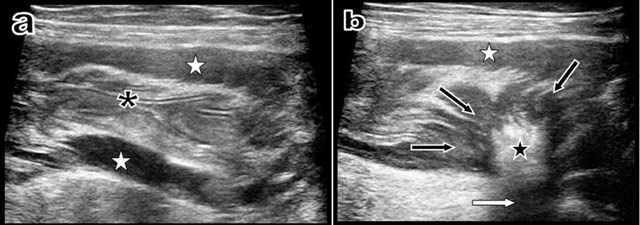

Figure 3

Longitudinal ultrasound view (a) of the descending colon just proximally to the stenosis shows that the colonic lumen is absolutely empty with normal mucosal folds (black asterisk). Nevertheless, hypertrophy of the muscular layers is evident (white stars). Another longitudinal ultrasound view (b) obtained just at the level of the retractile “scar-like” process shows the retractile centripedic convergence of the muscular layers (black arrows) towards a sharply well-delimitated hyperechoic (black star) and hyper-attenuating intraparietal scar (white arrow).